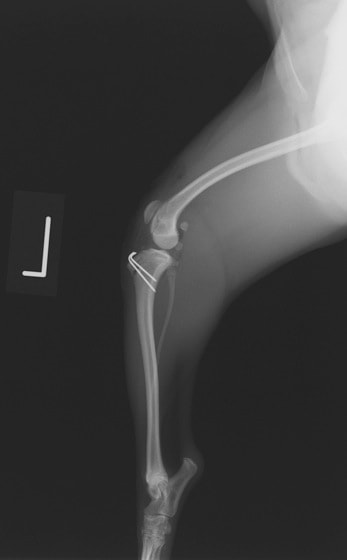

■ 症例22 ポメラニアン 1歳5か月 去勢雄

左後肢の挙上を主訴に来院した。整形学的検査、レントゲン検査より左右の膝蓋骨脱臼(左GradeⅡ〜Ⅲ、右Grade Ⅱ)を認めた。また、脛骨の前方引き出し試験の際に、引き出し兆候は認められないものの、疼痛が認められたため、前十字靭帯の損傷が疑われた。術中における、目視および関節内の操作によって、前十字靭帯の損傷や過伸展といった異常が認められなかったため、膝蓋骨脱臼の整復のみ実施した。手術手技は縫工筋及び内側広筋の解放、脛骨粗面の外側転位、滑車ブロック形造溝術、内外側関節包の縫縮を実施した。本症例は跛行もなく経過良好である。しかし、頸骨高平部の角度(TPA)が 右26.2°、左24.9°であり、解剖学的に前十字靭帯損傷のリスクが高いことから今後の経過に注意が必要である。